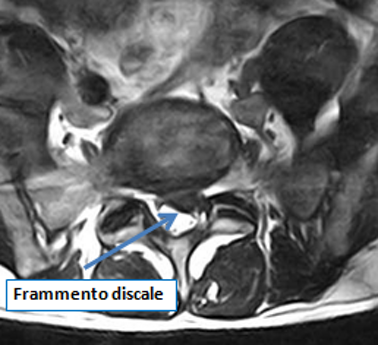

Il paziente presentava da 2 mesi dolore lombare con irradiazione alla coscia e ginocchio sinistro, del tipo cruralgia con associate intense parestesie (formicolii).

L’obbiettività neurologica evidenziava ipotonia del muscolo quadricipite femorale di sinistra.

Una risonanza lombare evidenziava un’ernia discale espulsa L2-L3 sinistra e migrata verso l’alto.

Le terapie farmacologiche avevano prodotto solo un parziale e non significativo miglioramento del dolore.

Il paziente optava per trattamento conservativo con ossigeno-ozono terapia.

Già dopo la seconda seduta, il signore beneficiava di un miglioramento della sintomatologia dopo 6 sedute di ozonoterapia e nel giro di 5 settimane recupero completo dell’autonomia lavorativa.

Dopo pochi mesi il signore ha potuto riprendere l’attività sportiva non agonistica.

A distanza di 12 mesi ha effettuato una nuova risonanza magnetica lombare, che ha documentato la completa scomparsa dell'ernia.

Per questo e numerosi altri casi documentati, vale sempre la non certezza della correlazione tra ozonoterapia ecoguidata e regressione dell'ernia.